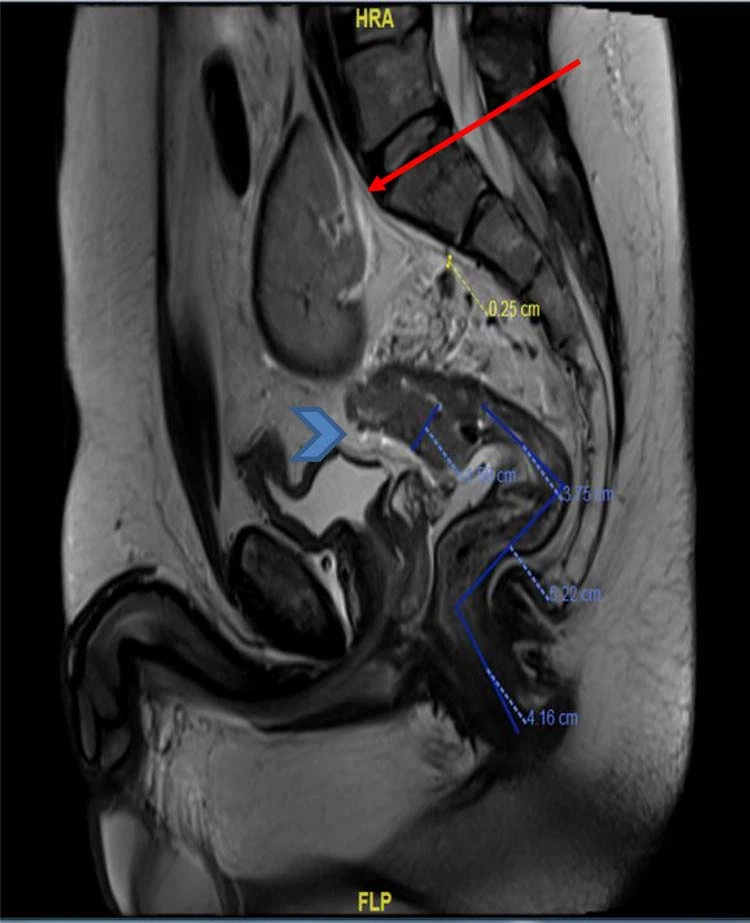

Figura 3. RM da pelve (visão sagital) mostrou massa retal superior com envolvimento da gordura mesorretal (ponta de seta) e rim pélvico ectópico (seta).

Um menino de 40-anos de idade, surdo e mudo, apresentou história de 4 meses de sangramento retal associado a alteração nos movimentos intestinais, sem dor abdominal, sem histórico de perda de peso e sem histórico familiar decâncer colorretal, sem história de uso de tabaco. Na avaliação clínica, ele parecia pálido com sinais vitais normais e seu exame mostrou um abdome mole, sem sensibilidade ou massas palpáveis ao toque retal revelou sangue, mas nenhum tumor palpável. A investigação laboratorial básica mostrou um nível de Hg de 8,6 g/dL. e nível de CEA de 4,8 ng/ml. Em investigação adicional, uma colonoscopia revelou uma grande massa retal circunferencial fúngica friável a 9 cm da borda anal estendendo-se até o cólon sigmóide distal, não obstrutiva com um comprimento de 8 cm e o restante do cólon era normal. Uma biópsia da massa foi feita e mostrou adenocarcinoma invasivo moderadamente diferenciado. Em rotina adicional de estadiamento radiológico, TC de tórax, abdome e pelve confirmou a massa retal superior com rim esquerdo mal rotacionado ectópico localizado no abdome inferior e pelve superior, oposto aos corpos vertebrais L5-S1 (Figs 1 e 2). Não havia doença peritoneal ou metástase à distância. Além disso, a RM da pelve mostrou novamente uma massa retal superior com invasão de gordura mesorretal e múltiplos linfonodos (T3N2) e confirmou um rim esquerdo ectópico (Figs 3 e 4).